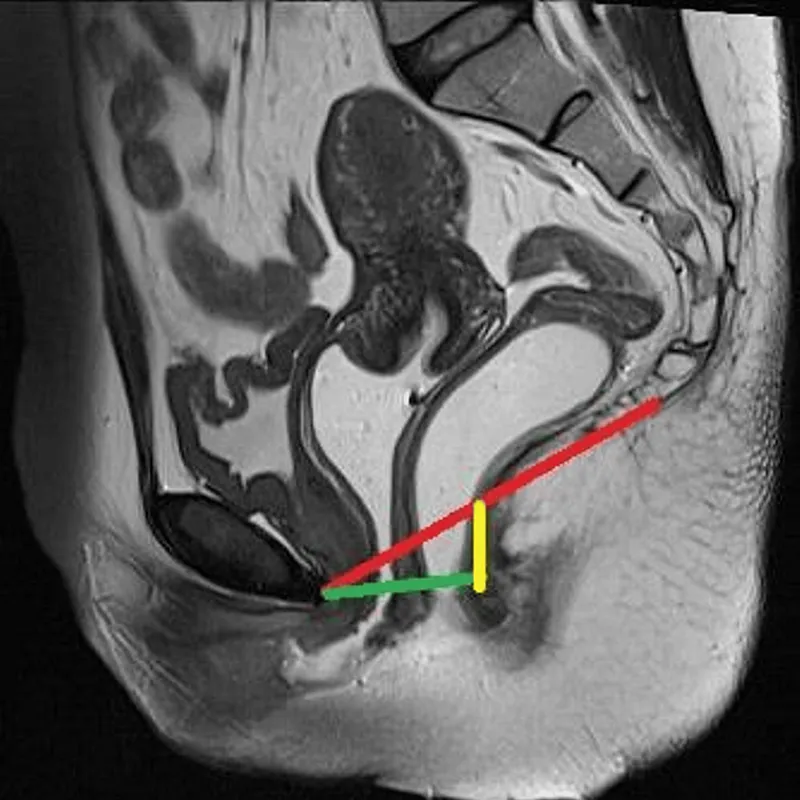

Rectocele & Enterocele: Diagnosis & Staging - Seeing & Scoring Sag

- Diagnosis:

- Clinical Exam: Valsalva maneuver, Sims speculum reveals posterior vaginal bulge.

- Differentiation:

- Rectocele: Bulge of rectum into posterior vagina.

- Enterocele: Herniation of small bowel (peritoneal sac) into upper posterior vagina, often superior to rectocele.

- Rectovaginal exam: Assesses rectovaginal septum integrity (thinned in rectocele).

- Staging Systems:

- POP-Q (Pelvic Organ Prolapse Quantification): Standard, objective. Point Bp (most distal point on posterior vaginal wall) is key for rectocele.

- Stage 0: No prolapse.

- Stage I: Leading edge >1 cm above hymen (value < -1 cm).

- Stage II: Leading edge between -1 cm and +1 cm relative to hymen.

- Stage III: Leading edge >1 cm below hymen, but < (TVL-2) cm. (TVL = Total Vaginal Length)

- Stage IV: Complete eversion; leading edge ≥ (TVL-2) cm.

- Baden-Walker System: Simpler, less precise (Grades 0-4).

⭐ Enterocele typically involves the herniation of the small bowel and is often found superior and posterior to a rectocele; it may become more apparent when the patient is standing or straining.